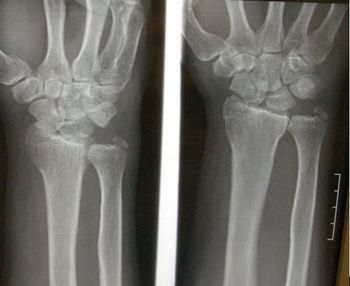

Progressive numbness in 3 fingers on both hands led this computer programmer to diagnose himself as having carpal tunnel syndrome. But, there's more to this story.

Test your radiographic skills with this emergency medicine case. Can you spot the injury? Is there more here than initially meets the eye?